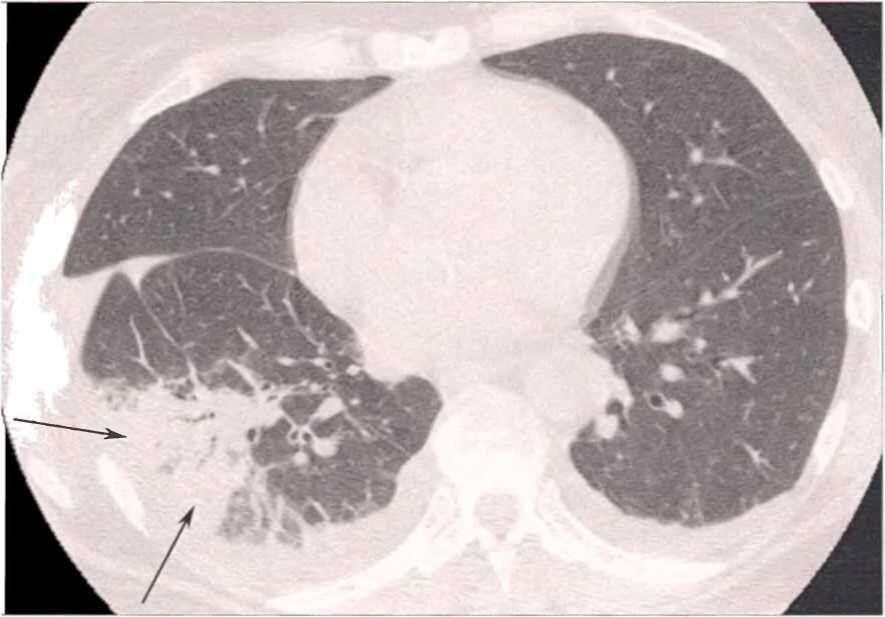

Но выявление у больного обширного поражения лёгких (более 80% поражения лёгких), которое на КТ определяется как множественные участки инфильтрации легочной ткани по типу «матового стекла», расположенные диффузно в легочной паренхиме обоих лёгких, является неблагоприятным прогностическим фактором и большим риском необходимости госпитализации в ОРИТ с назначением кислорода или переводом на ИВЛ.